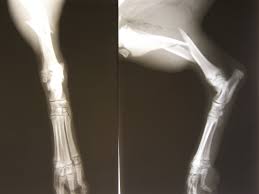

PEMF therapy was first made for non-union fractures, when the body can’t heal a break on its own. Now it’s common in orthopedics for cases like spinal fusion and congenital pseudarthrosis [4]. Devices like the Bone Growth Stimulator provide daily, gradual energy to tissues over time.

Although the process is slow, clinical trials show PEMF reduces pain and lowers the chance of fractures not healing. Research suggests PEMF works well with other electrotherapies to support bone healing, but more study is needed on how it affects function [5].

In veterinary research, PEMF has helped dogs with conditions like Legg-Calvé-Perthes disease [6]. It looks like a promising, non-invasive option compared to surgery [7].